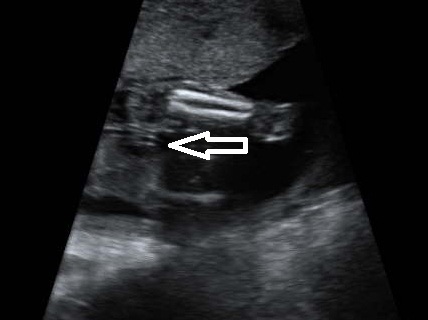

Pic from the femur measurment:

Attachment 10654

Ive put the arrows in